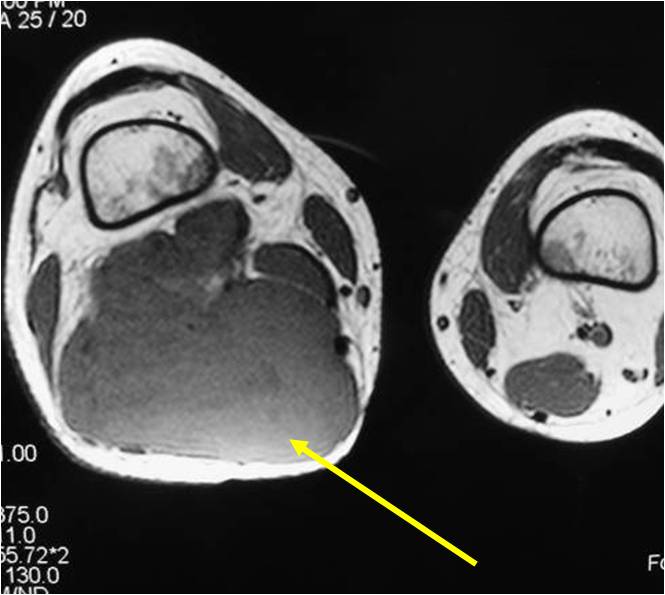

- Aggressive motheaten to permeative lesion

- Indistinct border in most cases

- Osseous destruction with a soft tissue component

- Chondroid matrix calcification may be present (60-70% of cases)

- Soft tissue mass

(Right Arrow) Cartilaginous Component